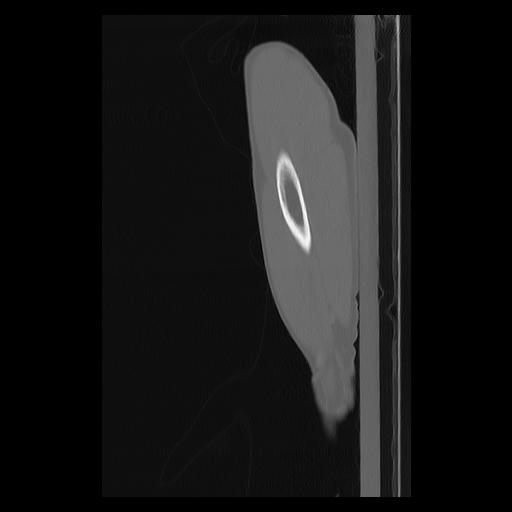

33 PULMON,CE,Sagittal,3.000,PULMON,Sagittal,